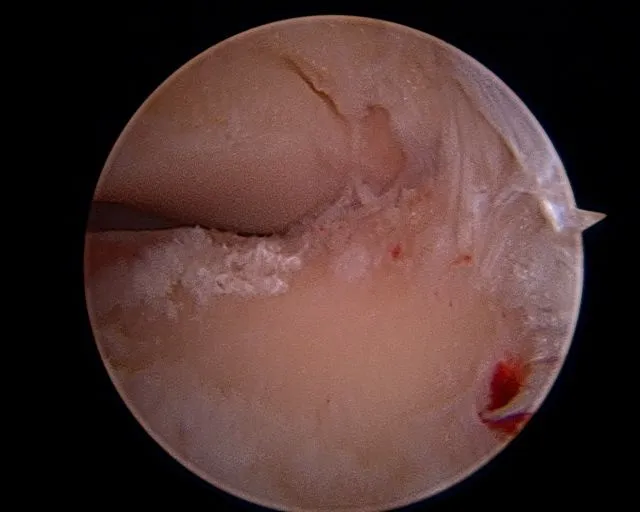

Intraoperative subtalar joint arthroscopy pics

Scarring in the subtalar joint

Scar tissue at the middle facet